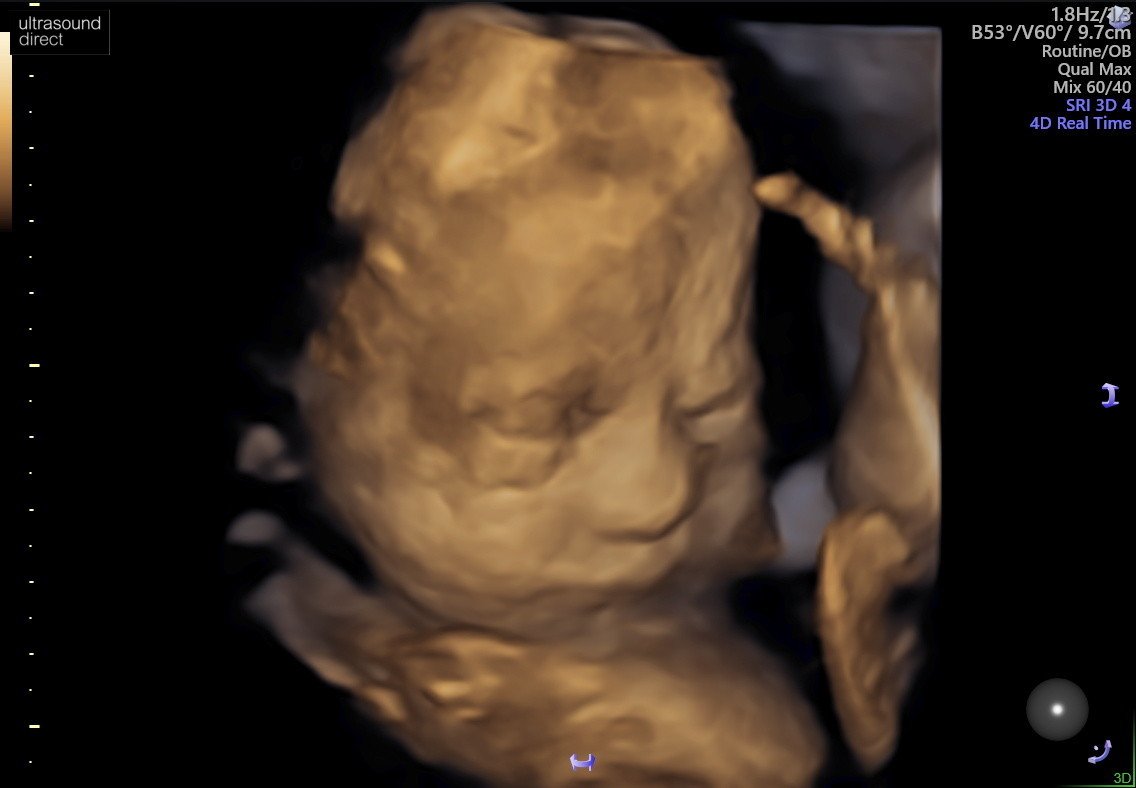

My mielismy USG, z malutka wszystko ok i tak jak of paru dni czuje, jest glowka do dolu. Wiem, ze to jeszcze wczesnie i moze sie obkrecic, ale mam nadzieje, ze tak zostanie.

download%20(2).jpeg